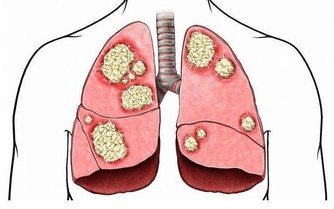

肝作為人體最為重要的代謝器官,如果肝不好的人,人的健康肯定是會受到影響的,而夜裡頻繁醒來,很可能就是肝出問題了。

肝臟是我們身體內的重要器官,也是較為脆弱且容易患病的一個器官。不僅病毒感染可以導致肝病,飲食不當乃至休息不當都會導致肝病的發生。所以,日常生活中除了充足的睡眠之外,飲食對於肝臟的保護就顯得格外重要。那麼如果你的身體產生這些症狀,該好好保護你的肝髒了!

那麼,當肝臟出現問題的時候,我們的人體會有哪些表現呢?以下羅列出了幾種。